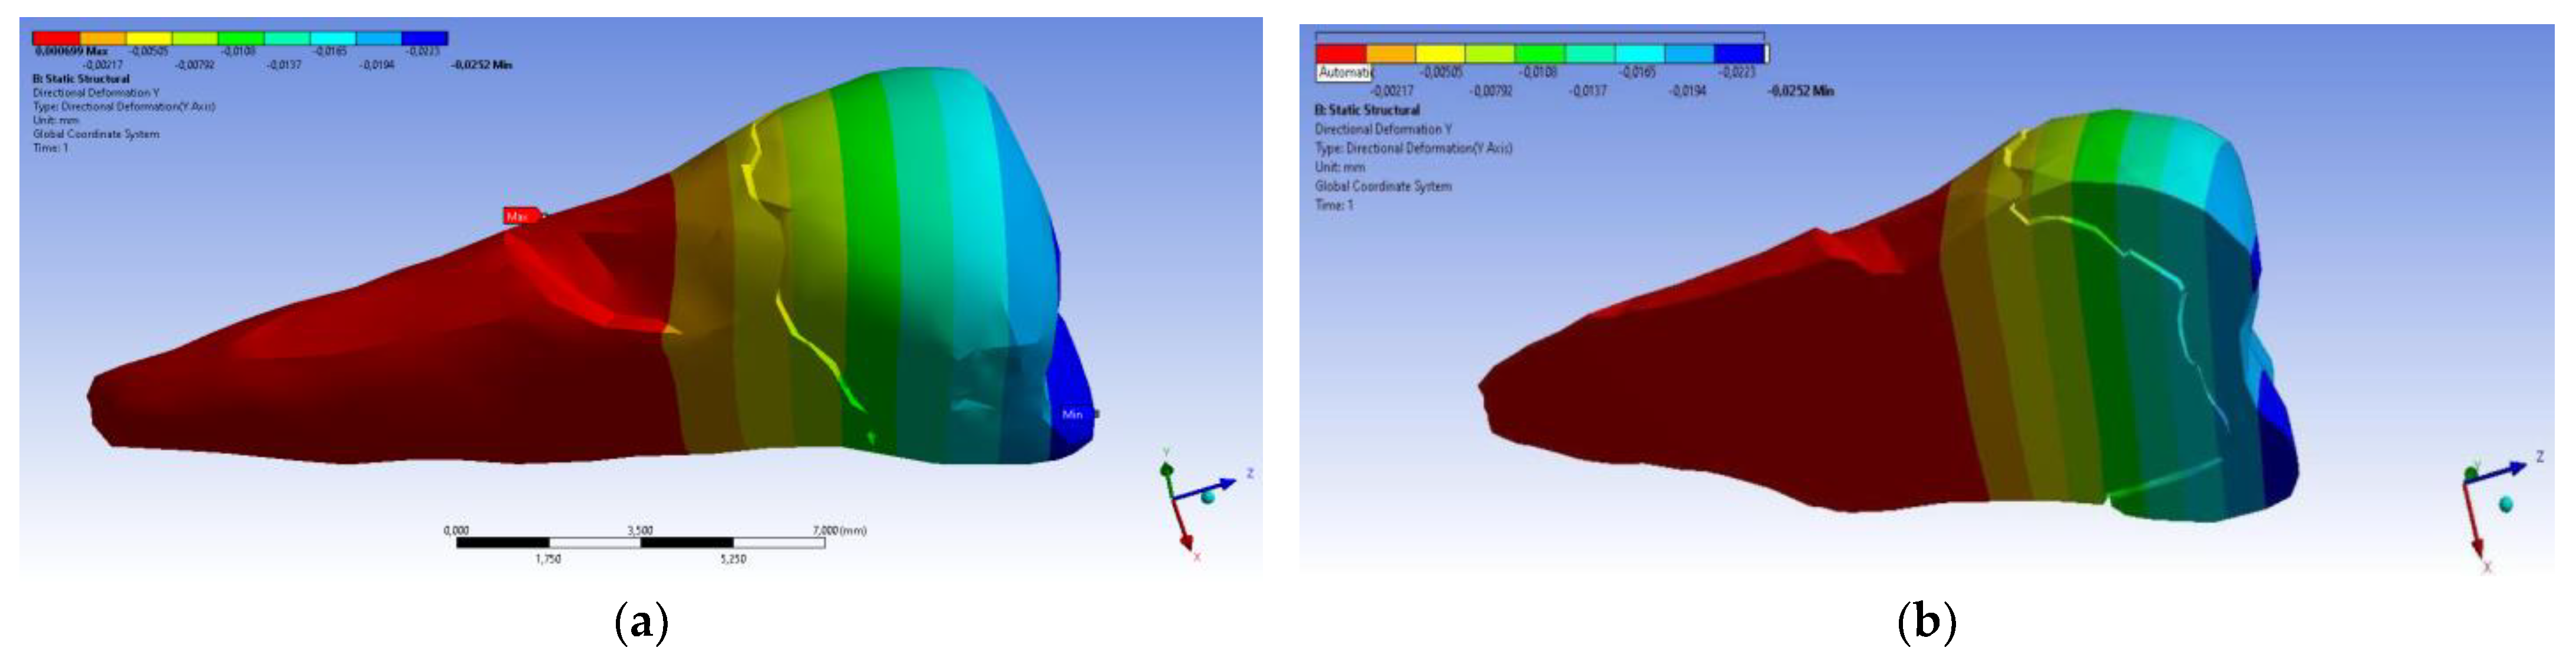

3. Finite Element Analysis (FEA) of Mandibular Right Premolars

| Minimum | 0 mm | −4.24 × 10−3 mm | −2.52 × 10−2 mm | −1.56 × 10−2 mm | 1.01 × 10−6 MPa | −35.6 MPa | −57.1 MPa | −104 MPa | −15.2 MPa | −152 MPa | −43.7 MPa | −39.6 MPa | −56.3 MPa |

| Maximum | 2.77 × 10−2 mm | 3.57 × 10−3 mm | 6.98 × 10−4 mm | 4.78 × 10−3 mm | 248 MPa | 61.5 MPa | 177 MPa | 72.2 MPa | 195 MPa | 21.4 MPa | 44.2 MPa | 117 MPa | 22.2 MPa |

| Minim. in | Cementum | Cementum | Enamel | Enamel | Cementum | Cementum | Enamel | Enamel | Enamel | Cementum | Enamel | Enamel | Cementum |

| Maxim. in | Enamel | Enamel | Cementum | Enamel | Cementum | Enamel | Enamel | Enamel | Enamel | Enamel | Cementum | Cementum | Cementum |